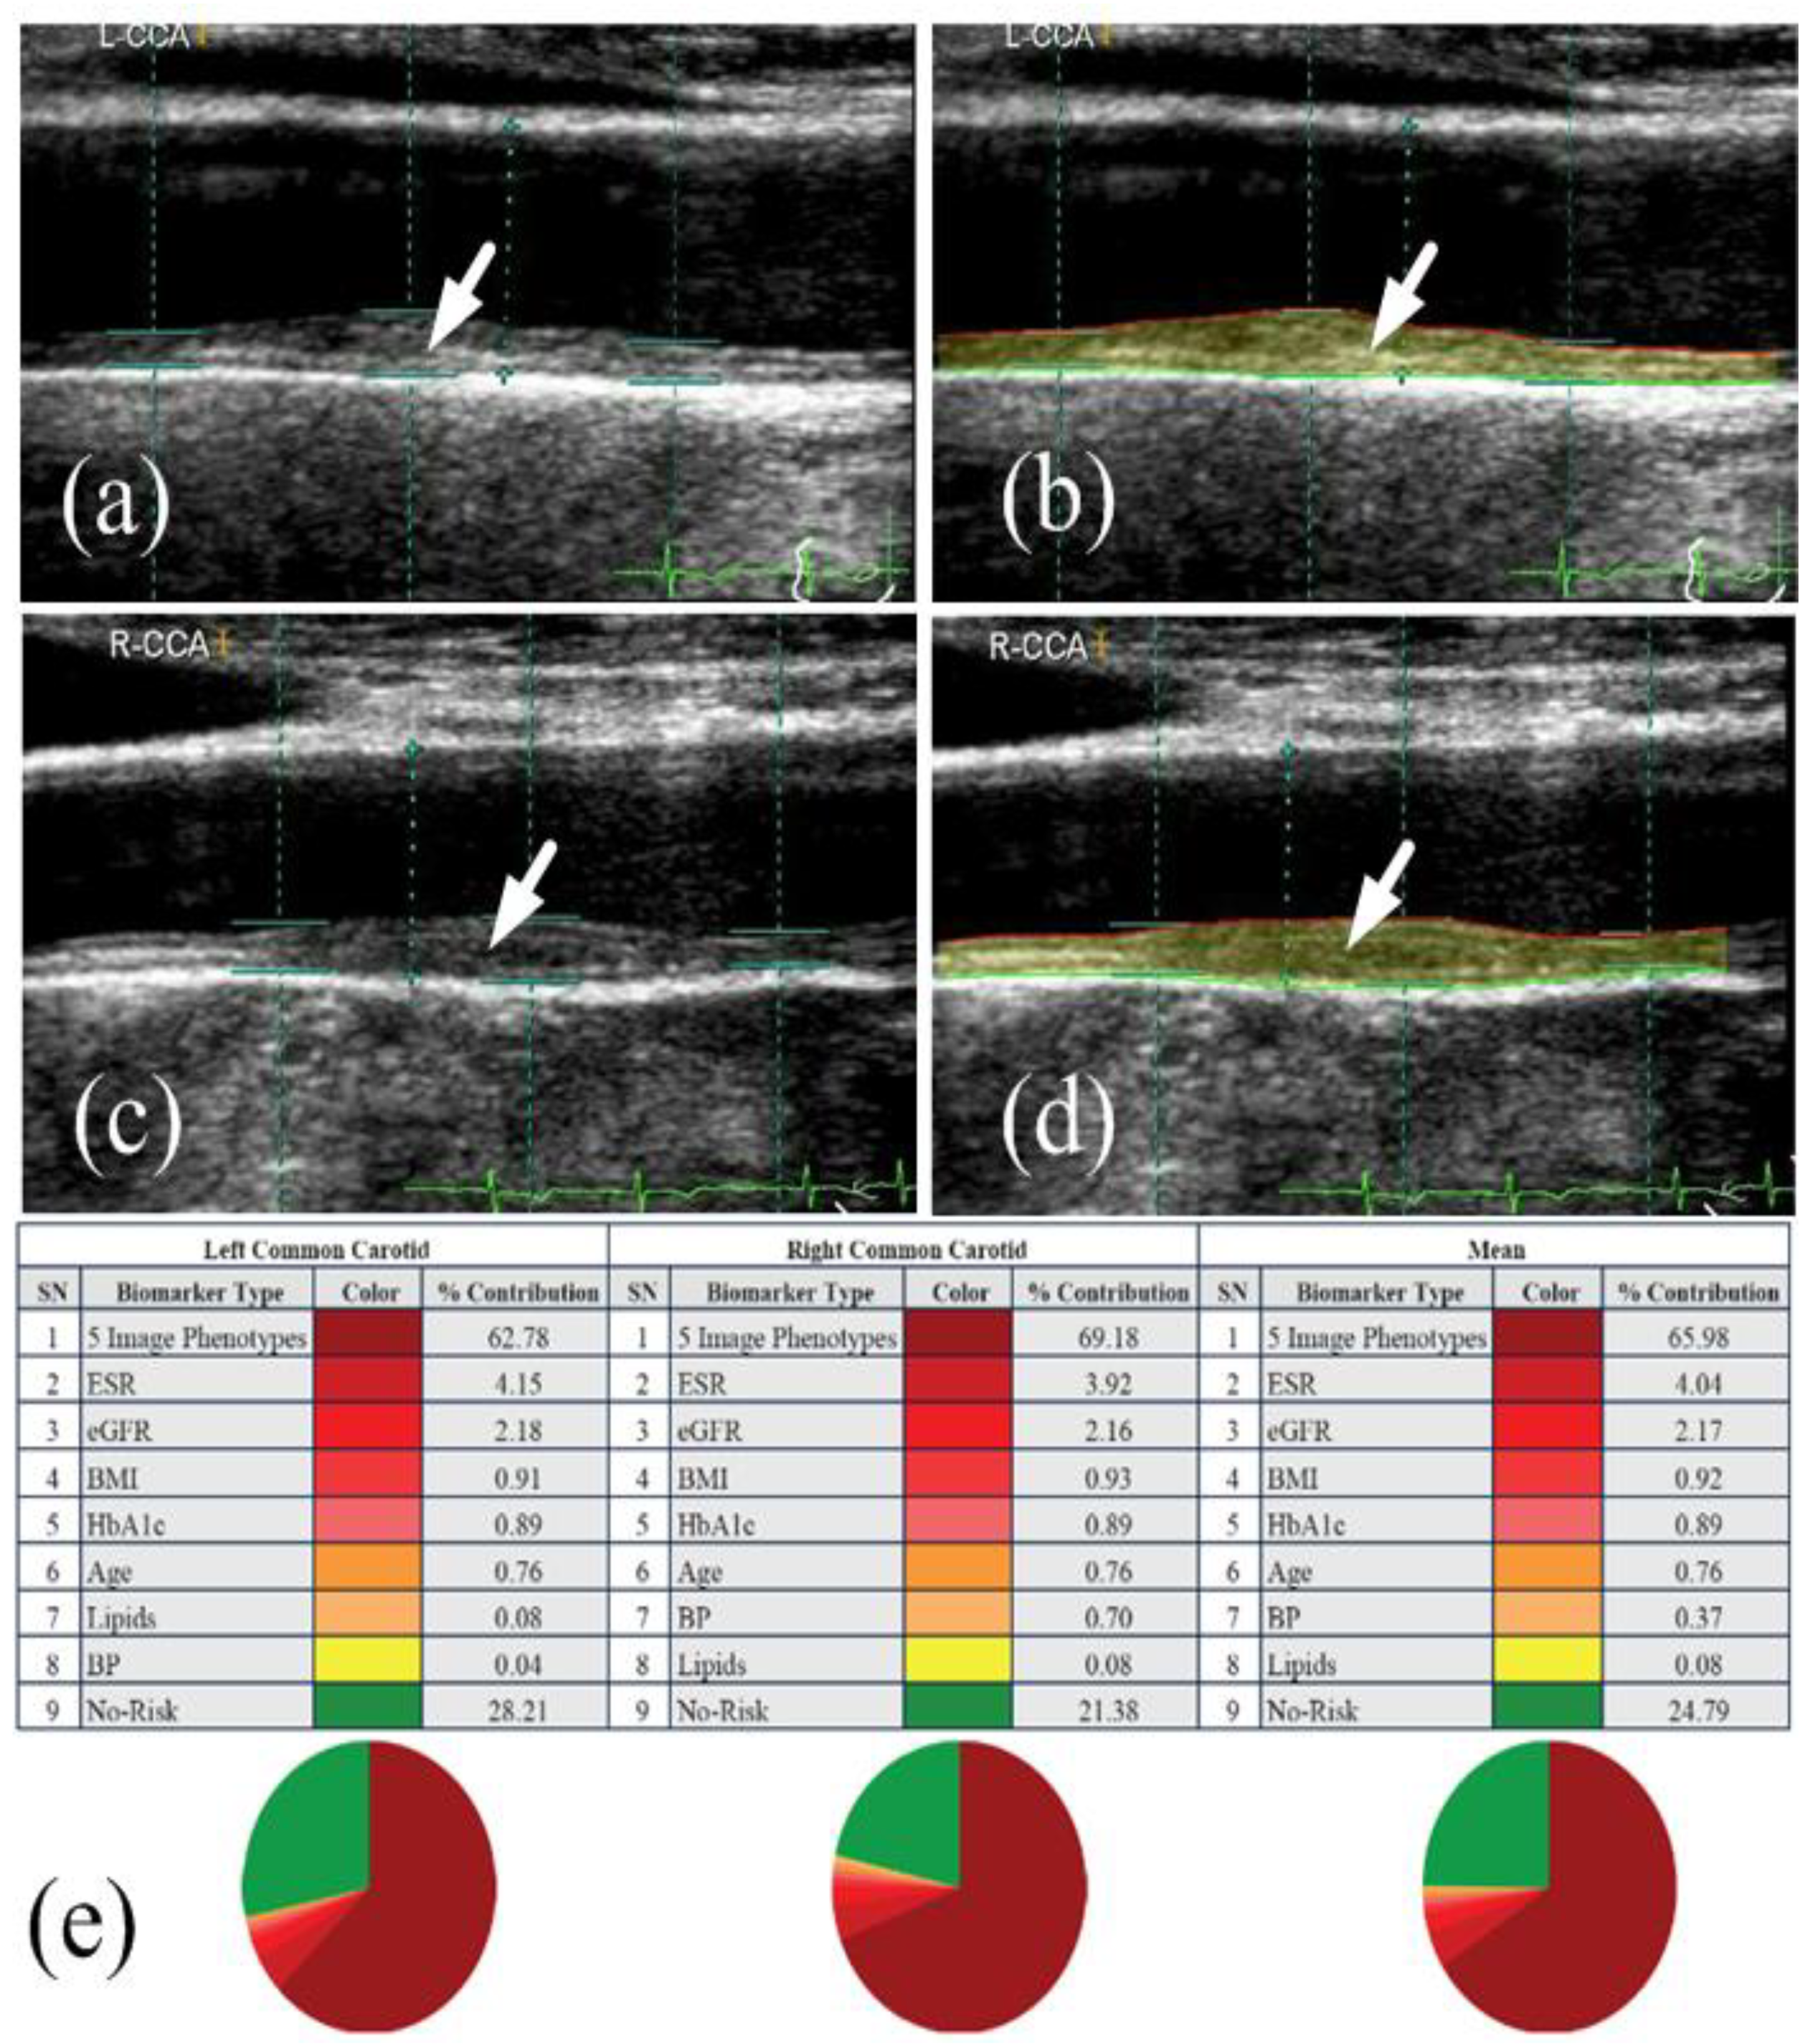

- Khanna, N.N.; Jamthikar, A.D.; Gupta, D.; Araki, T.; Piga, M.; Saba, L.; Carcassi, C.; Nicolaides, A.; Laird, J.R.; Suri, H.S.; et al. Effect of carotid image-based phenotypes on cardiovascular risk calculator: AECRS1.0. Med. Biol. Eng. Comput. 2019, 57, 1553–1566. [Google Scholar] [CrossRef]

- Jamthikar, A.; Gupta, D.; Khanna, N.N.; Saba, L.; Araki, T.; Viskovic, K.; Suri, H.S.; Gupta, A.; Mavrogeni, S.; Turk, M.; et al. A low-cost machine learning-based cardiovascular/stroke risk assessment system: Integration of conventional factors with image phenotypes. Cardiovasc. Diagn. Ther. 2019, 9, 420–430. [Google Scholar] [CrossRef] [PubMed]